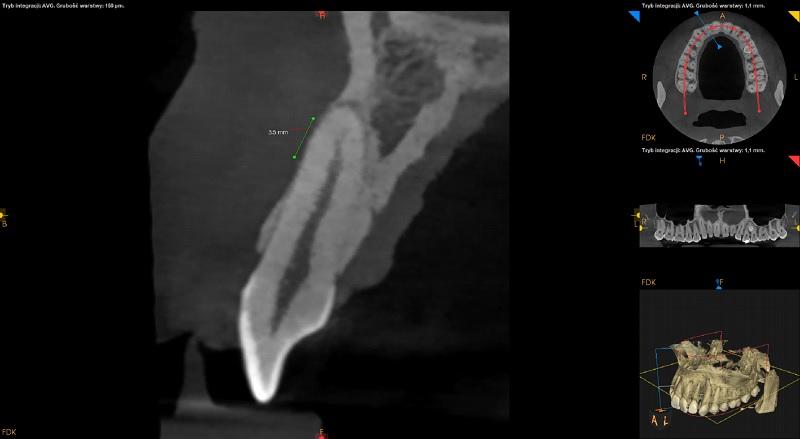

Pomiędzy korzeniami zębów 44 i 45 widoczny zatrzymany ząb dodatkowy. Położony pionowo. Wierzchołek korzenia zęba zagięty. Widoczna resorpcja korzenia zęba 44.

Pomiędzy korzeniami zębów 45 i 46 widoczny zatrzymany ząb dodatkowy. Położony pionowo. Widoczna resorpcja korzenia zęba 45 oraz korzenia mezialnego zęba 46. Poszerzenie mieszka wokół korony zęba (około 3,5mm) – do obserwacji.